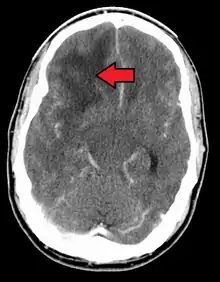

GBM in the frontal right lobe as seen on CT scan

When viewed with MRI, glioblastomas often appear as ring-enhancing lesions. The appearance is not specific, however, as other lesions such as abscess, metastasis, tumefactive multiple sclerosis, and other entities may have a similar appearance.[58] Definitive diagnosis of a suspected GBM on CT or MRI requires a stereotactic biopsy or a craniotomy with tumor resection and pathologic confirmation. Because the tumor grade is based upon the most malignant portion of the tumor, biopsy or subtotal tumor resection can result in undergrading of the lesion. Imaging of tumor blood flow using perfusion MRI and measuring tumor metabolite concentration with MR spectroscopy may add diagnostic value to standard MRI in select cases by showing increased relative cerebral blood volume and increased choline peak, respectively, but pathology remains the gold standard for diagnosis and molecular characterization.